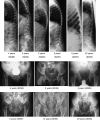

Schimke immunoosseous dysplasia (SIOD) is an autosomal recessive multisystem disorder characterized by prominent spondyloepiphyseal dysplasia, T cell deficiency, and focal segmental glomerulosclerosis. Biallelic mutations in swi/snf-related, matrix-associated, actin-dependent regulator of chromatin, subfamily a-like 1 (SMARCAL1) are the only identified cause of SIOD, but approximately half of patients referred for molecular studies do not have detectable mutations in SMARCAL1. We hypothesized that skeletal features distinguish between those with or without SMARCAL1 mutations. Therefore, we analyzed the skeletal radiographs of 22 patients with and 11 without detectable SMARCAL1 mutations. We found that patients with SMARCAL1 mutations have a spondyloepiphyseal dysplasia (SED) essentially limited to the spine, pelvis, capital femoral epiphyses, and possibly the sella turcica, whereas the hands and other long bones are basically normal. Additionally, we found that several of the adolescent and young adult patients developed osteoporosis and coxarthrosis. Of the 11 patients without detectable SMARCAL1 mutations, seven had a SED indistinguishable from patients with SMARCAL1 mutations. We conclude therefore that SED is a feature of patients with SMARCAL1 mutations and that skeletal features do not distinguish who of those with SED have SMARCAL1 mutations.